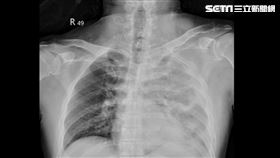

林正杰抗肺腺癌8年逝!8大症狀易誤認感冒

身為民進黨創黨元老之一的林正杰3日凌晨4時許病逝,享...

林珍羽不菸罹肺腺癌!8大症狀易誤認感冒

台灣民眾黨台北市議員林珍羽昨(22)日下午在臉書透露...

汪建民罹肺腺癌4期 8症狀「易誤認感冒」

56歲的汪建民以《台灣靈異事件》中「鐵頭」一角深植人...

母子竟先後揪出肺腺癌 醫揭驚人原因

57歲莊女士,家庭主婦,不抽菸、不喝酒、生活規律,在...